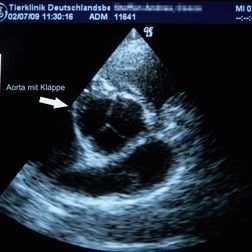

ekg

EKG – Elektrokardiogramm

Die elektrischen Aktivitäten des Herzmuskels werden hierbei aufgezeichnet. Dadurch lassen sich viele Erkrankungen erkennen.